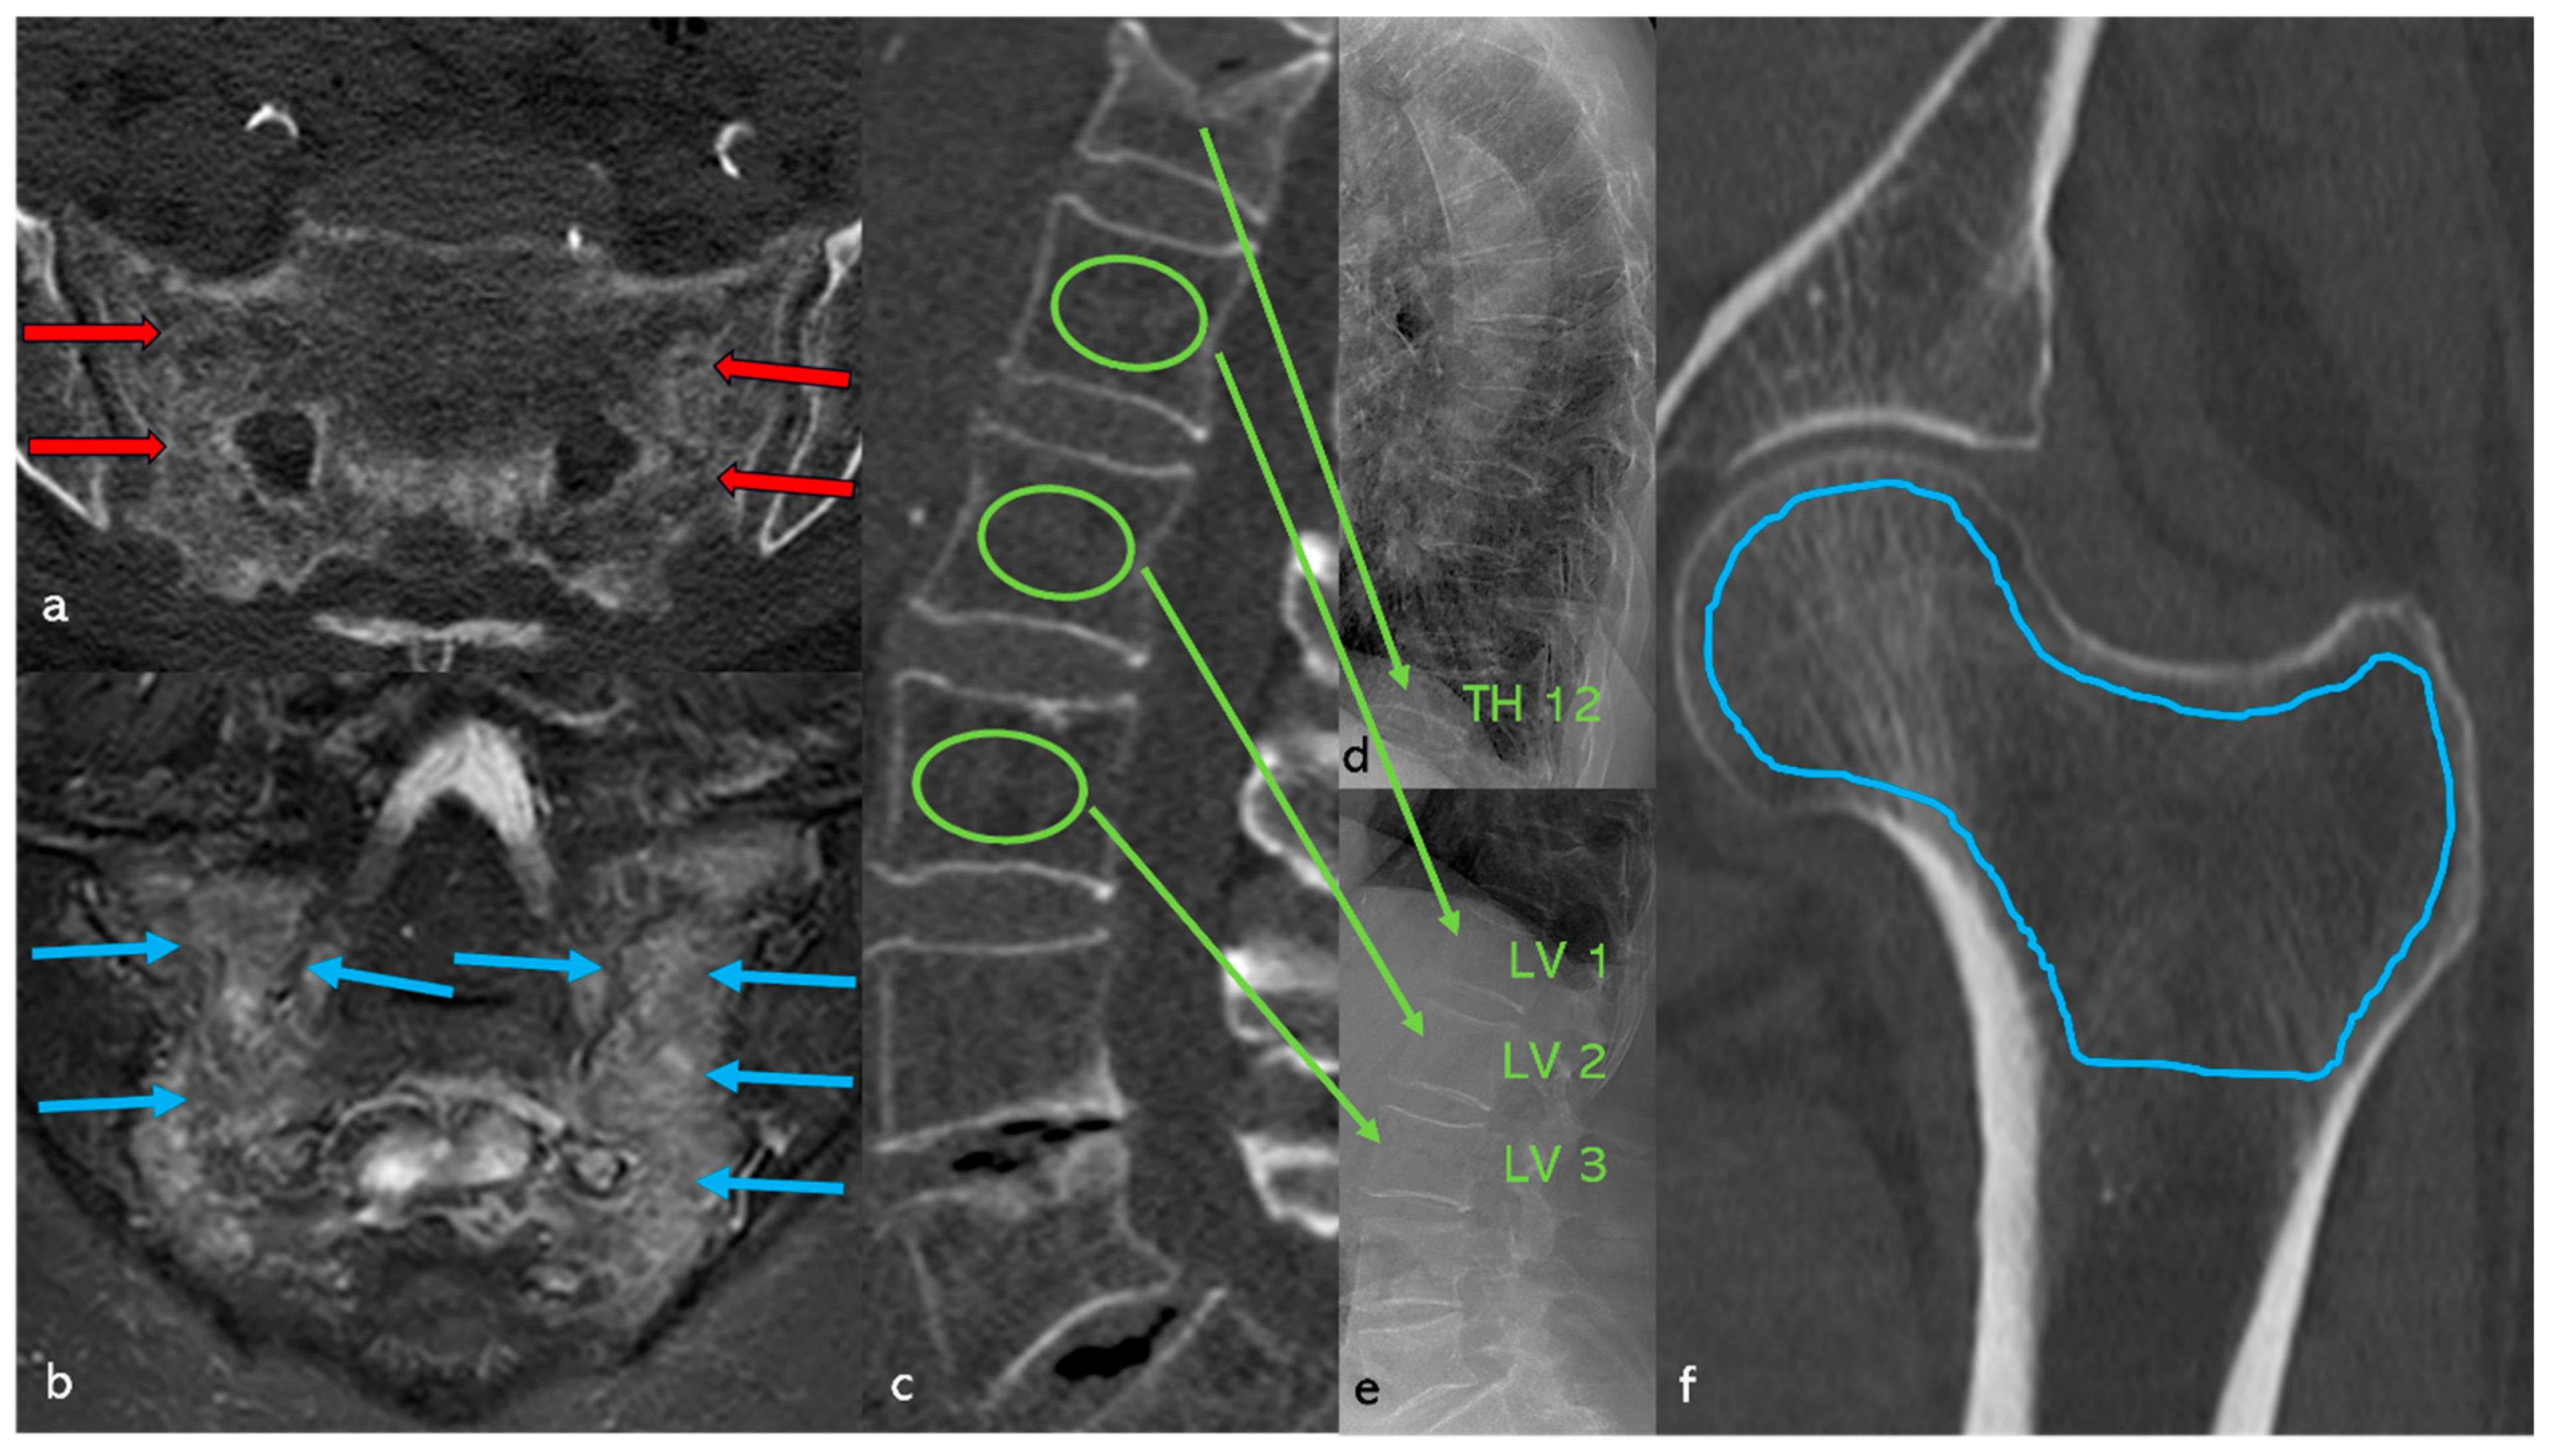

2.2. Determination of Bone Density

3.2.3. Fractures of the Axial Skeleton (Figure 6, Table 2)

3.8. Case Study (Figure 11)